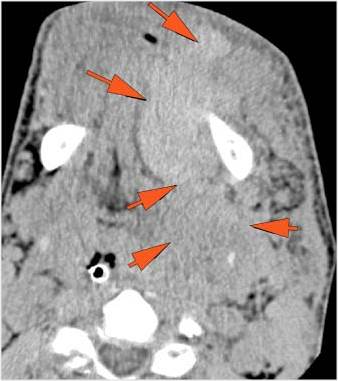

There is bony injury or displacement of the body, angle, ramus, parasymphyseal region, alveolar ridge, and condylar and coronoid process of the mandible. [In case of fracture, describe complexity and displacement]. [Yes/No]

There is entrapment of the muscles of mastication or other soft tissues by fractures of the coronoid process and/or zygomatic arch. [Yes/No]